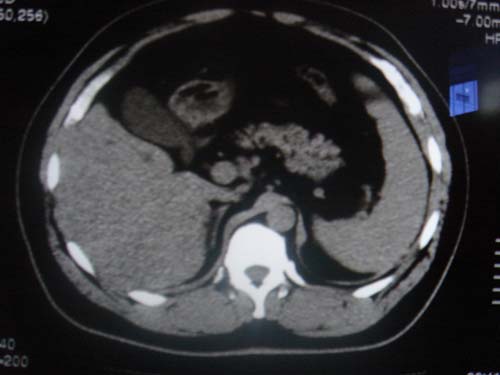

患者 男 40 右上腹不适 有胆囊息肉病史2年

本例就是胆囊比较大,内密度不很均匀,疑有砂砾状结石,未见息肉以及其他异常。

肝脏增大,

片中示肝脏的ct值低于脾脏,肝脏右叶外缘部份凹凸不平,考虑脂肪肝,肝硬化可能。结合其检查如b超或ct增强检查。

胆内胆管结石,第十二幅肝内似类圆形等密度灶.强化后再说吧或者做其它检查.

胆囊未见明显异常,肝脏密度似比脾脏密度低,测量一下ct值排除一下脂肪肝.当然做一下增强或mr就更好了.

肝右叶密度不均,脾大。强烈要求增强扫描除外浸润型肝癌。

肝大   密度降低  脾大  脂肪肝?